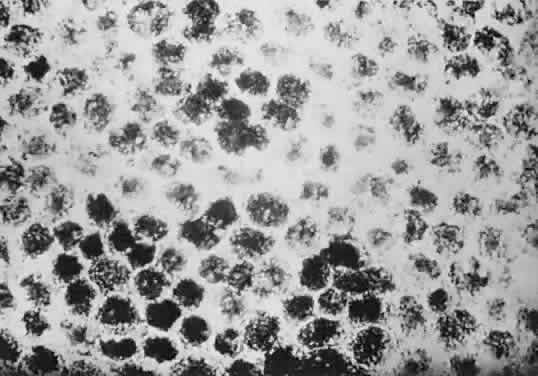

Histologically, congenital hypertrophy of the RPE is characterized by a monolayer of large RPE cells containing larger-than-normal pigment granules (Fig. 19; see Fig. 18B through E). Overlying photoreceptor elements have been shown to be degenerated, which explains the localized visual field defects corresponding to these areas.170

Fig. 19. A. Electron microscopic findings of normal-appearing retinal pigment epithelium (RPE) granules. B. Electron microscopy within area of congenital hypertrophy of the RPE shows enlarged pigment granules and a thickened basement membrane (bm) of the RPE cells. (Buettner H: Congenital hypertrophy of the retinal pigment epithelium. Am J Ophthalmol 79:177, 1975)

Histologically, the involved RPE cells are taller and contain a greater concentration of pigment granules (which may be enlarged) than normal RPE (Fig. 21). The overlying retina has been shown to be unaffected in one patient.171